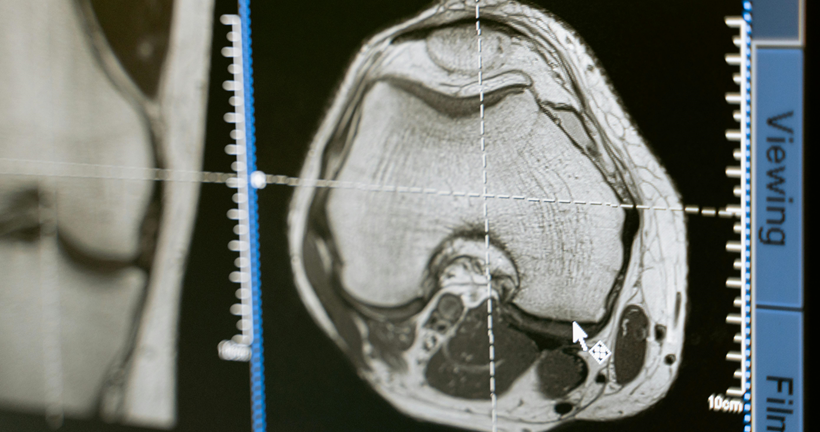

Resonancia magnetica y PET-FDG en la demencia frontotemporal variante conductual: revisión sistemática

Cristian SantiagoJácome Granda | Investigador La demencia frontotemporal (DFT) es una enfermedad neurodegenerativa compuesta por un conjunto de síntomas comportamentales y del lenguaje como consecuencia de la atrofia de áreas que pertenecen a lóbulo temporal y frontal. Según las características clínicas, la DFT se subdivide en tres variantes. La demencia frontotemporal variante semántica (DFTvnf) que se presenta con alteraciones en el lenguaje, principalmente en la capacidad de comprender y reconocer objetos. La demencia frontotemporal no fluente (DFTvnf) se manifiesta por una marcada disminución en la fluidez, fallo en la emisión de sonidos, así como agramatismo y la demencia frontotemporal variante conductual (DFTvnf) de la cual haremos énfasis en esta investigación, es una enfermedad neurodegenerativa poco estudiada y de inicio insidioso, que se caracteriza por la presencia de síntomas comportamentales y cognitivos que repercuten en el desenvolvimiento adecuado en las distintas actividades de la vida diaria. Dentro de la clínica presentada por pacientes que presente este tipo específico de variante se encuentra disfunción ejecutiva, apatía y desinhibición, además de la disminución en la empatía, alteraciones en los hábitos alimenticios y conductas estereotipadas marcadas, en ocasiones, se manifiesta mediante comportamientos compulsivos y conductas sexuales desinhibidas; los sujetos pueden presentarse agresivos, con una higiene personal desalineada, hiperoralidad, así como coprolalia. A pesar de que este cuadro es el más frecuente, existen perfiles caracterizados por la adinamia y la falta de iniciación. La presentación sintomatológica de la disfunción frontal dependerá de si la afectación predominante inmiscuye a regiones del cíngulo u orbitales. Además, las afectaciones de las funciones ejecutivas dependerán del daño en la corteza dorsolateral. Buscamos describir la relación existente entre la atrofia cerebral identificada en estudios de resonancia magnética estructural, PET-FDG y su implicación cognitiva sobre los pacientes con DFTvnf. La revisión sistemática se realizó bajo los criterios establecidos en la declaración PRISMA, considerando 80 estudios de las bases de datos Pubmed y ScienceDirect en donde por criterios de inclusión y exclusión la revisión final se realizó con 40 artículos de las bases de datos antes descritas. Como resultados en relación con los estudios analizados, se encontró que solo el 15% de artículos mantienen una correlación de áreas anatómicas - cognitivas, además se encontraron alteraciones en los dominios de atención, memoria y funciones ejecutivas mientras que los hallazgos de atrofia cerebral se localizan en áreas frontales, el cíngulo e ínsula. El diagnóstico de la DFTvnf es un proceso complejo que se compone de distintas etapas, por lo que, la presente revisión sistemática confirma la importancia de estudio de las manifestaciones clínicas, la evaluación neuropsicológica de procesos cognitivos y el papel de las técnicas de neuroimagen en la identificación de este tipo de variantes. Estos resultados contribuirán a obtener un diagnóstico oportuno y veraz de la DFTvnf, describir las manifestaciones clínicas de manera más específica además de beneficiar a los profesionales del área para la implementación de intervenciones adecuadas que permitan mejorar la calidad de vida de quienes la padecen. Leer el artículo completo

DR. CRISTIAN E. LEYTON Y DR. RAMÓN LANDIN-ROMERO | FACULTY OF HEALTH SCIENCES, THE UNIVERSITY OF SYDNEY. SYDNEY, AUSTRALIA. En los últimos años el interés científico en las enfermedades neurodegenerativas ha crecido considerablemente. Esto ha sido motivado por el gran incremento en el número de personas afectadas por estas dolencias, unido al advenimiento de nuevas técnicas y métodos de evaluación que han posibilitado un mejor conocimiento sobre las mismas. En los últimos 10 años, grupos internacionales de investigadores han actualizado los criterios diagnósticos de demencia, incorporando el uso de imágenes cerebrales y otros marcadores biológicos en la valoración del juicio clínico. Las demencias frontotemporales son un conjunto amplio y heterogéneo de enfermedades neurodegenerativas que afectan frecuentemente a pacientes menores de 65 años. Se manifiestan a nivel clínico con cambios graduales en la personalidad y en el lenguaje, a diferencia de la enfermedad de Alzheimer que se asocia a una pérdida gradual de la memoria. Las demencias frontotemporales también se asocian con la acumulación tóxica de al menos dos proteínas distintas en las neuronas, mientras que la enfermedad de Alzheimer se caracteriza exclusivamente por la acumulación de ovillos neurofibrilares y placas de amiloideas en el cerebro. De acuerdo con la prominencia de las manifestaciones clínicas, las demencias frontotemporales pueden clasificarse en dos grandes grupos; la variante conductual y la variante afásica, esta última también referida como afasia progresiva primaria. La variante conductual cursa con cambios larvados de la personalidad y comportamiento. Estos síntomas son a veces difíciles de determinar y cuantificar, debido a que su valoración clínica depende del relato del cónyuge, familiares, amigos o colegas del paciente. Frecuentemente los familiares relatan conductas sociales inapropiadas, pérdida del decoro y cortesía, como también falta de empatía y contacto social, y pérdida de interés en pasatiempos. En muchos casos, las alteraciones conductuales dan lugar a conflictos conyugales, problemas interpersonales o dificultades laborales que pueden camuflar los síntomas primarios de la enfermedad y retrasar el diagnóstico. Debido a que este tipo de demencia afecta mayoritariamente a personas menores de 65 años, los síntomas también se pueden confundir con crisis existenciales, episodios depresivos, trastorno bipolar u otras alteraciones psiquiátricas propias de esta edad. La evaluación de las funciones mentales superiores, de gran relevancia en la demencia frontotemporal, se efectúa mediante una evaluación neuropsicológica. Ésta puede evidenciar deterioros en la capacidad para ejecutar actividades complejas que requieren habilidad de planificación, jerarquización y resolución de conflictos. No obstante, la evaluación de estas habilidades (también conocidas como funciones ejecutivas) presenta ciertas limitaciones, ya que muchos pacientes con demencia frontotemporal muestran un rendimiento limítrofe o dentro del rango normal en comparación con personas sanas de la misma edad. Nuevas técnicas como la resonancia magnética nuclear, permiten visualizar la anatomía del cerebro con gran detalle en pacientes con demencia en vida. El estudio de resonancia cerebral es además fundamental para descartar otras posibles causas de demencia, como la presencia de tumores o de enfermedad cerebrovascular. Las imágenes de resonancia en pacientes con demencia frontotemporal detectan una reducción significativa del tamaño de la parte delantera del cerebro, que incluye la parte inferior de los lóbulos frontales y la parte anterior de los lóbulos temporales. Sin embargo, en estadios temprano de la enfermedad, los cambios cerebrales son sutiles y muchas veces el clínico debe observar la progresión de los síntomas para establecer un diagnóstico certero. La ausencia de síntomas clínicos claramente definidos ha motivado que los criterios diagnósticos actuales estratifiquen el grado de certeza diagnóstico en tres niveles; definitivo, posible y probable. El diagnóstico definitivo se establece cuando el examen histológico revela cambios patológicos en el cerebro y/o cuando existe en el paciente una mutación genética causante de la enfermedad. El diagnóstico posible se establece ante la presencia progresiva de los cambios conductuales y/o fallos en pruebas neuropsicológicas. Por último, el diagnóstico probable requiere además la presencia de cambios en las imágenes cerebrales y un deterioro funcional significativo en las actividades de la vida diaria. En el otro espectro clínico de la demencias frontotemporales están las afasias primarias progresivas. En contraste con la variante conductual, las afasias progresivas presentan un deterioro progresivo del lenguaje que es bastante evidente para el paciente y familiares. Característicamente, las alteraciones del lenguaje son relativamente aisladas y respetan otros dominios cognitivos, al menos durante las fases iniciales de la enfermedad. La presentación afásica, sin embargo, exhibe un amplio rango de alteraciones del lenguaje que afectan la capacidad para comprender o producir palabras u oraciones adecuadamente. Los criterios actuales definen tres variantes clínicas; semántica, no-fluente/agramática y logopénica, cada una de las cuales presentan un patrón único de alteración lingüística, distribución de atrofia cerebral y patología asociada. La variante más enigmática es la variante semántica o también conocida como la demencia semántica. La alteración lingüística cardinal es la pérdida del significado de las palabras y una reducción del vocabulario, que es reflejo de una disolución del conocimiento conceptual sobre el mundo. La demencia semántica se asocia a una desintegración de la información enciclopédica que se acumula a largo de la vida que causa dificultades no sólo para reconocer objetos y palabras, sino que también para identificar a las personas, sonidos y canciones. Las personas con demencia semántica pueden pasar desapercibidas, ya que presentan un lenguaje fluido, se incorporan con facilidad a una conversación y realizan actividades cotidianas de forma normal, al menos al inicio de la enfermedad. Las imágenes cerebrales muestran de manera consistente una reducción del tamaño de la parte anterior de los lóbulos temporales y la patología microscópica muestra la acumulación anormal de una proteína llamada ‘TDP-43’. La variante no-fluente/agramática, como su nombre lo indica, se caracterizada por dificultades para articular palabras, y construir y comprender oraciones. Sin embargo, al contrario de la variante semántica, la comprensión del vocabulario está preservado. Las imágenes cerebrales muestran una reducción de la masa cerebral de la parte inferior del lóbulo frontal izquierdo (área de Broca), un área que tiene un rol establecido en el habla y procesamiento morfosintáctico. La patología microscópica muestra acumulación anormal de una proteína llamada ‘tau’. Finalmente, la variante menos conocida, pero no menos importante, es la afasia logopénica, cuyo vocablo es derivado del griego y literalmente significa “escasez de palabras”. Como su nombre lo indica, las personas con la afasia logopénica presentan dificultades para encontrar palabras, lo que genera constante interrupciones y circunlocuciones. En contraste con otras variantes, no hay distorsiones en el habla y el conocimiento de las palabras está preservado. Sin embargo, estos pacientes muestran dificultades para evocar las palabras a pesar de conocerlas. En algunos casos, la construcción de las palabras es defectuosa debido a la transposición, reemplazo o desplazamiento de sílabas, que se hace más evidente con palabras más largas. La repetición de oraciones está consistentemente alterada, no solamente debido a los errores silábicos mencionados, sino que también por la incapacidad de retener todos los componentes de la oración en la memoria de corto plazo. Las imágenes cerebrales demuestran atrofia de la parte lateral del hemisferio izquierdo, en la unión entre el lóbulo temporal y lóbulo parietal. De forma importante, y en contraste con otras variantes de demencia frontotemporal, la mayoría de los casos de afasia logopénica, se asocian a con cambios microscópicos propios de la enfermedad de Alzheimer. Este hecho es de gran relevancia, ya que demuestra que la enfermedad de Alzheimer puede presentarse sin alteraciones en la memoria, pero con importantes problemas en la producción del lenguaje. En tan solo una década, el mundo de la investigación en demencias ha experimentado un notable desarrollo. Sin embargo, nuevos paradigmas son necesarios para comprender cómo la acumulación de las ciertas proteínas promueve distintos patrones de atrofia cerebral que a su vez dan lugar a la emergencia de diversos síndromes clínicos. Uno de los grandes desafíos de la neurociencia actual es, no solamente la detención del desastroso avance de estas enfermedades, sino además la determinación precoz de los síntomas. La identificación de mecanismos genéticos asociados al riesgo de desarrollar demencia a lo largo de la vida, servirá para implementar a tiempo intervenciones que puedan modificar, o mejor aún, detener la progresión de la neurodegeneración antes de la aparición de los primeros síntomas.